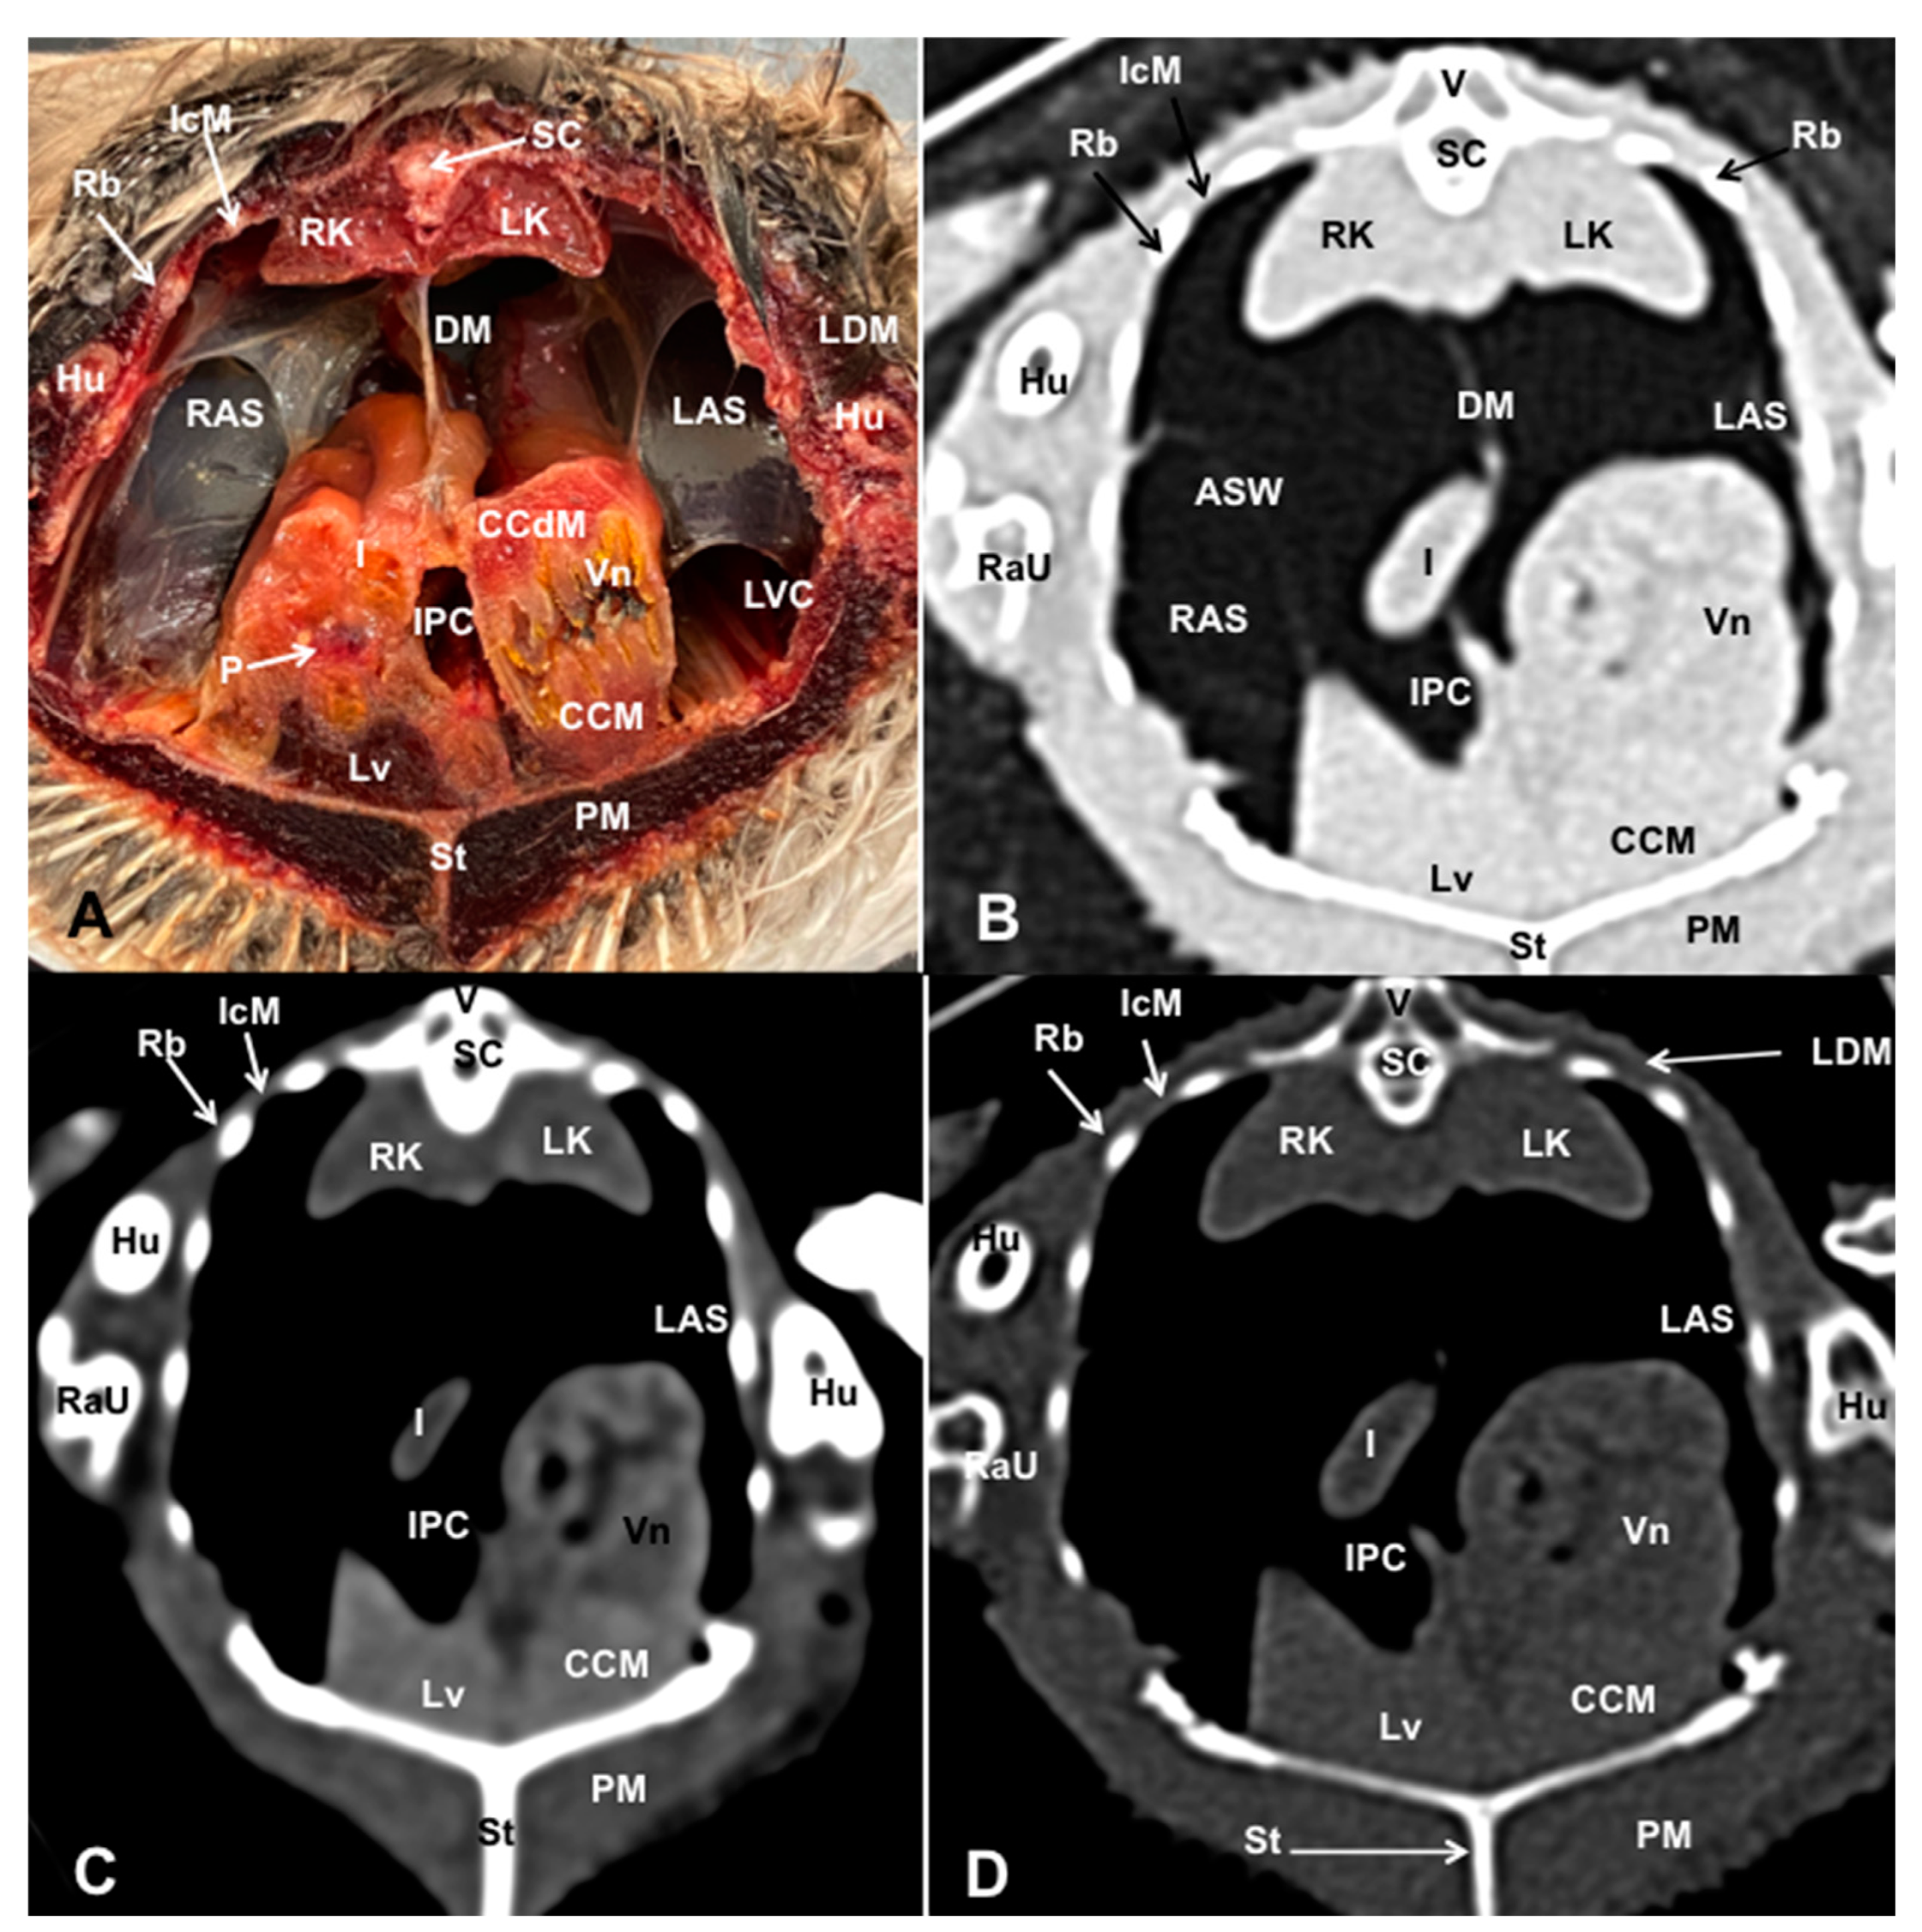

3.1. Anatomical Dissections and Cross-Sections

3.2. Computed Tomography Images